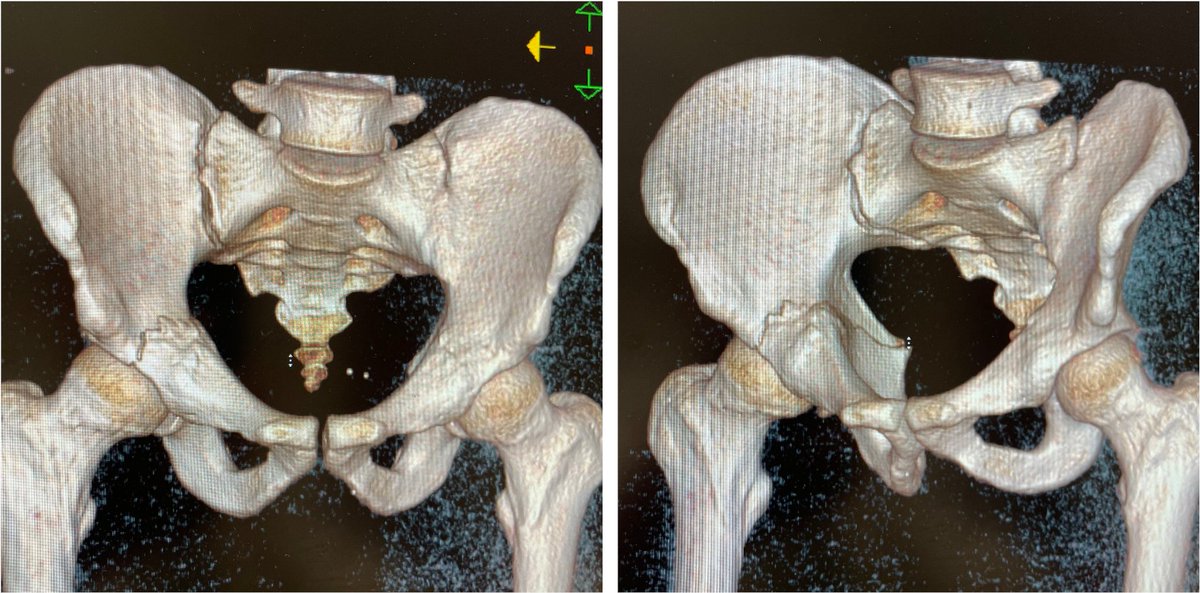

Percutaneous acetabular fixation

Dr. Diego López tweet mediaDr. Diego López tweet mediaDr. Diego López tweet media